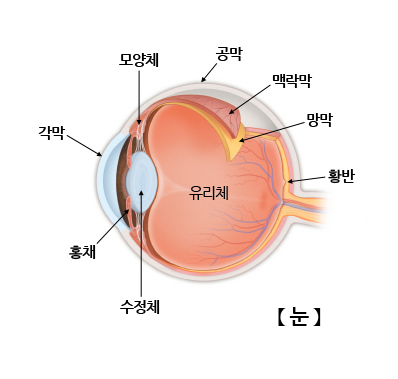

눈의 길이는 24mm 정도이며 탁구공만한 크기입니다. 눈의 구조는 역할에 따라 공막과 포도막, 망막으로 나눌 수 있습니다.

공막은 안구의 가장 바깥 층으로 흰색을 띄고 있으며 눈의 모양을 유지시켜줍니다. 각막과 빛을 굴절시키는 방수, 수정체, 유리체액이 공막내에 존재합니다.

포도막은 혈관막이라고 하며, 홍채와 맥락막을 포함합니다. 포도막은 풍부한 혈관으로 눈에 산소와 영양분을 공급해줍니다.

망막은 눈의 가장 안쪽 층에 있으며 신경이 분포하는 층입니다. 망막 중 빛이 직접 도달하는 부분을 황반이라고 하며, 여기서 가장 세밀하게 빛을 감지합니다.

눈은 시각정보를 뇌에 전달하는 시각기관으로 그 기능은 카메라와 비슷합니다. 시각정보가 들어오면 각막과 수정체는 이미지가 망막에 투영되도록 빛을 굴절시킵니다. 홍채는 각막과 수정체 사이에 존재해서 카메라의 조리개처럼 들어오는 빛의 양을 조절합니다.

들어온 빛은 유리체를 통과해서 최종 망막에 초점이 맞추어지며, 망막에 맺힌 이미지는 시신경을 통해 뇌로 전달되어 본 것을 인지하게 됩니다.